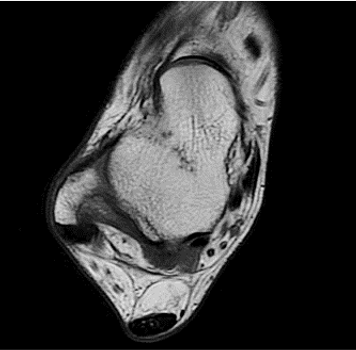

Conventional

384 x 256 (4 NEX)

3:00 minIAI (Innovative AI)

384 x 256 (2 NEX)

1:29 minscan time reduced up to 50%